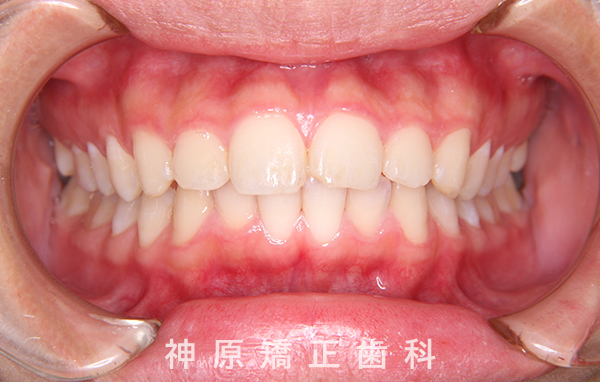

治療終了

治療前と治療後

口元の突出感を改善するために小臼歯の抜歯が必要と判断しました。抜歯スペースを活用し、前歯を可能な限り後方へ移動させるため、上下に矯正用アンカースクリューを使用する計画です。患者様とご家族に十分な説明を行い、治療ゴールに同意を得た上で矯正治療を開始しました。矯正治療の結果、側貌はE-lineに調和したバランスの良い仕上がりとなりました。